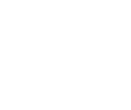

Most lesions were of lymph nodal origin (29/48 = 60.42%). The cervical lymph node group was most frequently affected (17/48 = 35.42%), followed by the axillary group (7/48 = 14.58%) and inguinal group (2/48 = 4.17%). The most common extranodal sites were the retroperitoneum (5/48 = 10.42%) and stomach (4/48 = 8.33%). The frequency of lesional sites is detailed in Table 3.

Most lesions were of lymph nodal origin (29/48 = 60.42%). The cervical lymph node group was most frequently affected (17/48 = 35.42%), followed by the axillary group (7/48 = 14.58%) and inguinal group (2/48 = 4.17%). The most common extranodal sites were the retroperitoneum (5/48 = 10.42%) and stomach (4/48 = 8.33%). The frequency of lesional sites is detailed in Table 3.